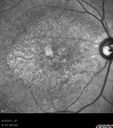

36-year-old man was seen by me in the office on August 23, 2012. I started seeing him years ago. His father in fact is an ophthalmologist. He started to notice vision change sometime in his early twenties. He has had progressing macular atrophy and unfortunately has poor vision in the left eye. The right eye continues to see decently. VISUAL ACUITY: OD 20/40, OS 20/200. IOP: OD 10, OS 12. The lenses are clear. EXTENDED OPHTHALMOSCOPY: OD: Vertical C/D ratio is 0.3. The macula looks atrophic. OS: Vertical C/D ratio is 0.3. The macula looks atrophic. The retinal vessels are fine. FUNDUS PHOTOGRAPHY - INFRA RED: The image shows hypopigmentation centrally. SPECTRALIS-SD-OCT SCAN: The OCT scan shows retinal atrophy in the center of both eyes with loss of the outer retinal layers. The choroid looks unusual in him, almost like the choriocapillaris is thinned out and the large choroidal vessels are more abundant. FUNDUS PHOTOGRAPHY - AUTO FLUORESCENCE: The image shows a ring of hyper auto fluorescence in the posterior pole within the macular arcades, which is a linear bright ring. Inside of that there is some hypo auto fluorescence, but not terribly so and he does seem to have decreased macular pigment in both eyes. IMPRESSION: 1. PROBABLE CONE DYSTROPHY – BOTH EYES AUTOSOMAL RECESSIVE DISCUSSION: I explained to the patient now that genetic testing is available, I think it would be best to characterize his dystrophy toward the goal of having genetic testing done and then ultimately and possibly, if it becomes available, offering him some sort of treatment.

dystcone_chsa_082313_07.jpg

Macular possible Cone Dystrophy - Fundus Autofluorescence667 views00000

dystcone_chsa_082313_08.jpg

Macular possible Cone Dystrophy - Fundus Autofluorescence965 views00000